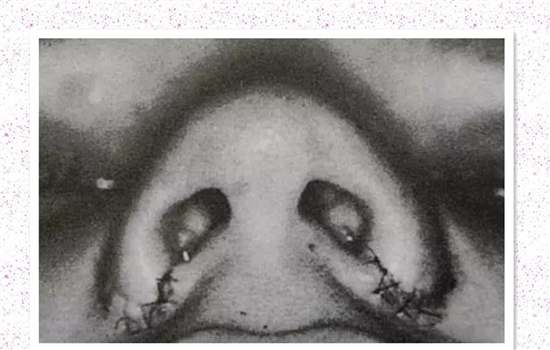

一边已经切除缝合,一边还未进行,在不改变鼻孔大小的情况下,两侧鼻翼已经明显不同,大家比较下: